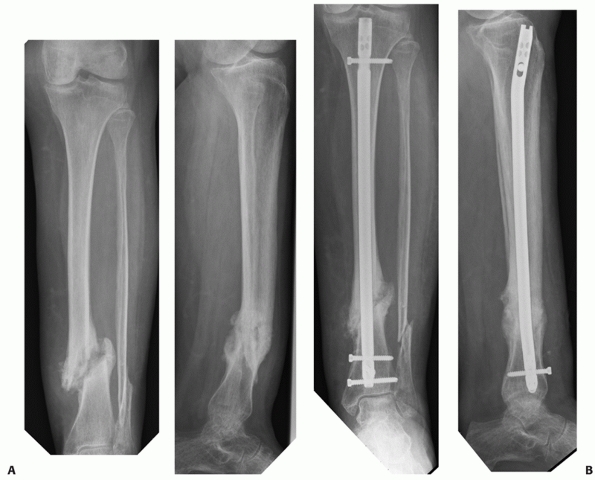

surgeons, it can be seen that intramedullary nailing can be considered

the implant of choice for tibial shaft fractures (Fig. 55-9).26 Indeed, Court-Brown19

reviewed 1106 tibial shaft fractures managed by reamed intramedullary

nailing, this being the largest series to date (level of evidence: 4).

The overall infection rate following intramedullary nailing of closed

tibial shaft fractures was 1.9% and the aseptic nonunion rate was 4.4%.19 For open fractures, infection rates increased from 6.9% for Gustilo type I injuries to 16.9% for Gustilo type IIIB injuries.66

The nonunion rates seen in those with open fractures also increased

from 12.1% for Gustilo type I injuries to 49.2% in patients with

Gustilo type IIIB injuries.66 There

![]() |

|

FIGURE 55-9 A. An unstable OTA A3.3 fracture. B. It was treated successfully with a locked reamed intramedullary nail.